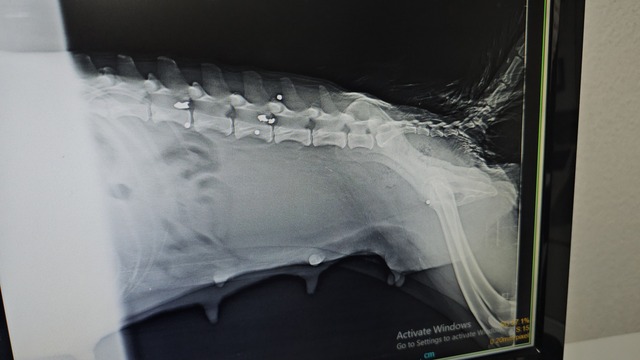

Köpeğin yaralı, yavrularının ise yeni doğmuş olarak geldiğini söyleyen veteriner hekim Ömer Faruk Alkan, "Röntgeni çekip muayene ettikten sonra yakın mesafeden ateş edildiğini, saçmaların omuriliğin içine ve vücuduna saplandığını gördük." dedi.

Omurilikteki saçmayı arka tarafı felç kalacağı için bulup çıkarttıklarını kaydeden Alkan, "Omuriliğin etrafındaki kemik dokusunu serbestleştirerek oradaki sinirin baskısından kurtardık. Sonra yavrularının yanına koyduk. Bir hafta kadar fizik tedavi uyguladık ama 1 ayakta felç olduğunu gördük. Hiç his yoktu. O ayak ve kuyruğu ampute ettik. Diğer ayakta da fizik tedavisi sürüyor. Fizik tedavide lazer ve yürütme egzersizleri yapıyoruz. Şu an ilk geldiğine göre çok iyi ama uzun süre tedavi görmesi gerekecek. Yavruların durumu çok iyi sadece 1 tanesini kaybettik. O da aldığı silah yarasından olabilir. Yavrular bize yeni doğmuş şekilde geldi" dedi.